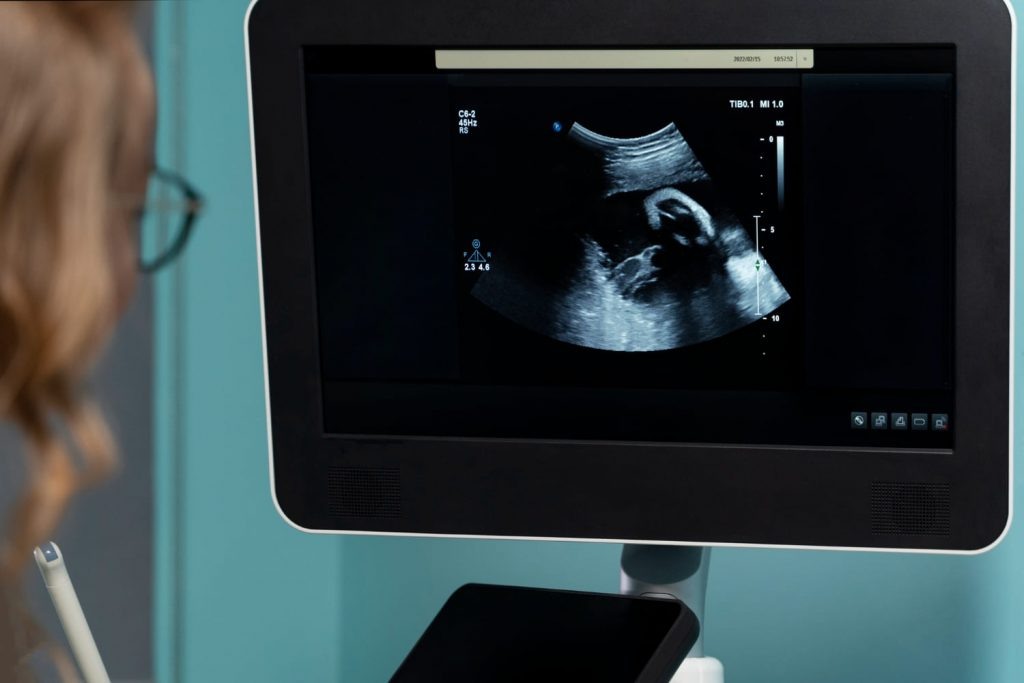

Врачи впервые предотвратили развитие тяжелого генетического заболевания — спинальной мышечной атрофии — с помощью лечения, которое ребенок получил еще в утробе матери. Двухлетняя девочка, которой грозило тяжелое генетическое заболевание, вероятно, стала первым человеком, успешно излеченным от болезни двигательных нейронов еще до рождения. Случай, описанный в New England Journal of Medicine, демонстрирует эффективность пренатальной генной терапии при спинальной мышечной атрофии — заболевании, которое до недавнего времени считалось практически неизлечимым. Новый подход к лечению опробовали по инициативе родителей девочки, ранее потерявших ребенка от того же заболевания. Будущая мать с 32-й недели беременности в течение шести недель принимала препарат «Рисдиплам». Это малая молекула, которая модифицирует экспрессию гена SMN2 и заставляет его производить больше жизненно важного белка SMN. Анализы амниотической жидкости и пуповинной крови подтвердили, что препарат успешно достигал плода. По

Двухлетняя девочка, которой грозило тяжелое генетическое заболевание, вероятно, стала первым человеком, успешно излеченным от болезни двигательных нейронов еще до рождения. Случай, описанный в New England Journal of Medicine, демонстрирует эффективность пренатальной генной терапии при спинальной мышечной атрофии — заболевании, которое до недавнего времени считалось практически неизлечимым.

Новый подход к лечению опробовали по инициативе родителей девочки, ранее потерявших ребенка от того же заболевания. Будущая мать с 32-й недели беременности в течение шести недель принимала препарат «Рисдиплам». Это малая молекула, которая модифицирует экспрессию гена SMN2 и заставляет его производить больше жизненно важного белка SMN.

Анализы амниотической жидкости и пуповинной крови подтвердили, что препарат успешно достигал плода. После рождения девочка продолжила принимать лекарство и, вероятно, будет получать его на протяжении всей жизни. По сравнению с другими детьми с аналогичным диагнозом, у ребенка обнаружены более высокие уровни белка SMN в крови и значительно меньшие признаки повреждения нервов.